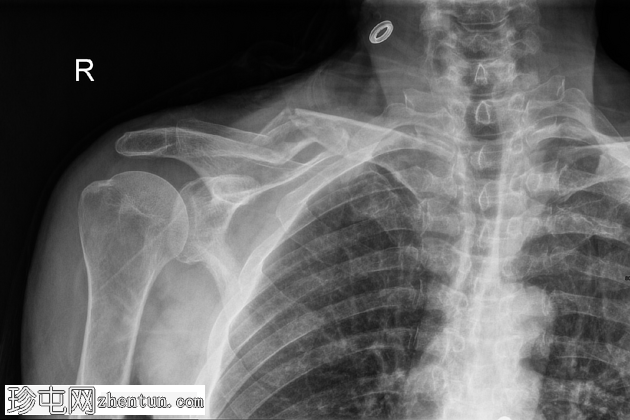

正面

右侧锁骨中段呈Z形粉碎性骨折,近端内侧骨折块向上移位,远端外侧骨折块向下移位,内侧骨折处软组织轻度膨出。

可见衣物痕迹覆盖锁骨内侧区域。肩锁关节和胸锁关节保存完好,胸腔内未见相关肋骨骨折或气胸。